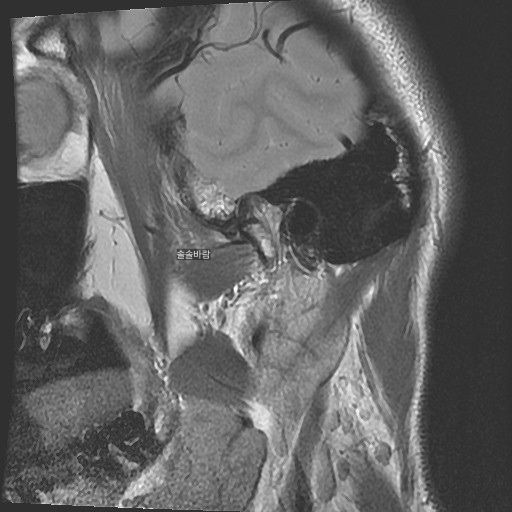

구강내과 턱 MRI 어느 사진이 우측? 좌측?인지 어떻게 보나요? 디스크 두꺼워짐 심한가요?ㅜ

어느 사진이 우측? 좌측?인지 어떻게 보나요?

그리고 사진 상 디스크 두꺼워짐 심한가요?ㅜ

• 2번 째 사진

현재 사진만으로는 정확히 왼쪽이나 오른쪽이다 라고 할 수 없습니다. 이는 데이터 상의 reference가 필요하며 보통은 해당 부위가 질문자님 기준으로 좌측일 가능성이 가장 크나 이는 좌우 반전을 할 수 있기 때문에 무조건 좌측이라고 할 수 없습니다. 현재 개구시와 폐구시에 보았을 때 condyle (아래턱 부위의 일부)가 disc를 넘어가지 못하고 있으며 이러한 경우 개구제한이 있거나 넘어가더라도 소리가 나면서 넘어갈 수 있습니다. 일부 염증도 보이고 있으므로 내과적인 치료를 하셔야 할 것으로 보입니다.